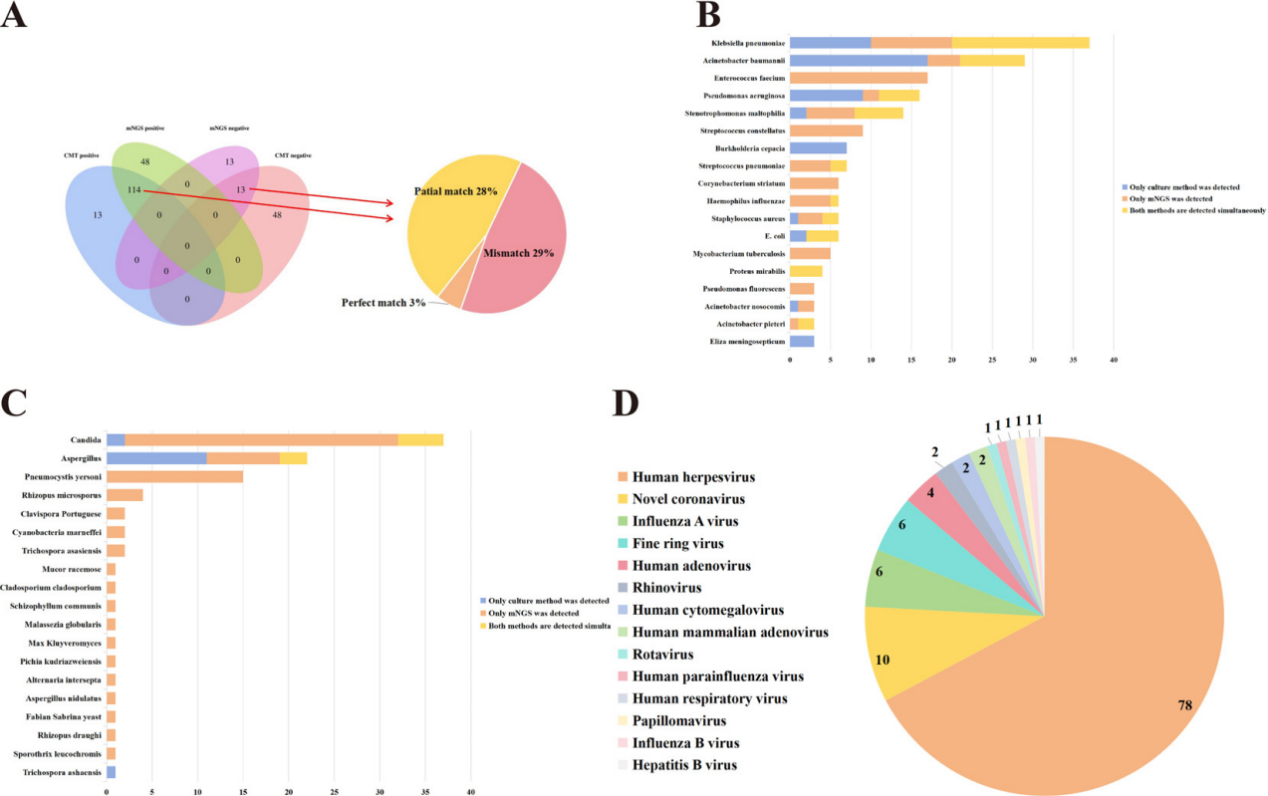

Figure.. Comparison of CMTs and mNGS results. (A) The detection results of CMTs and mNGS. (B) Comparison of Culturing and mNGS results (Bacteria). (C) Comparison of Culturing and mNGS results (Fungi). (D) Virus classification identified via mNGS.

The results of the study reveals that mNGS detected pathogens in 86% of cases, significantly outperforming CMTs, which identified pathogens in only 67% of cases. Spectrum of detected pathogens results showed that mNGS identified 59 bacteria, 18 fungi, 14 viruses, and 4 special pathogens while CMTs detected just 28. This enhanced detection capability provides clinicians with a more comprehensive diagnostic tool for pulmonary infections.

The mNGS excels at detecting atypical pathogens, such as Mycobacterium tuberculosis, Mycoplasma pneumoniae, Chlamydia psittaci, and fungal infections like Pneumocystis jirovecii and Talaromyces marneffei. These pathogens, often missed by traditional methods, were successfully identified by mNGS.